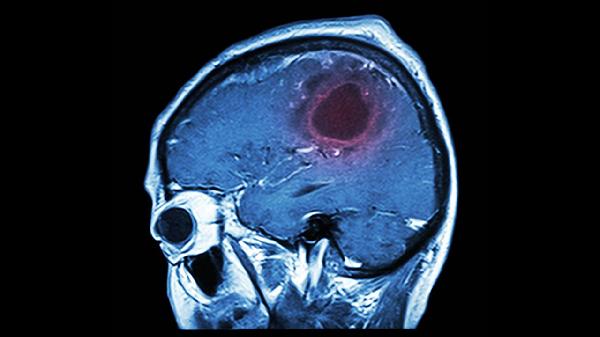

脑溢血的症状是什么

脑溢血的症状包括突发剧烈头痛、呕吐、意识障碍、肢体无力或麻木、言语不清等,需立即就医。脑溢血是一种危及生命的疾病,及时识别症状并采取急救措施至关重要。

3、意识障碍。脑溢血会迅速影响大脑功能,导致患者出现意识模糊、嗜睡甚至昏迷。意识障碍的程度与出血部位和出血量密切相关。